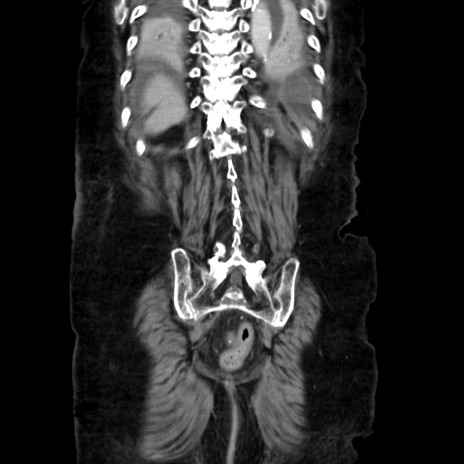

矢状断像